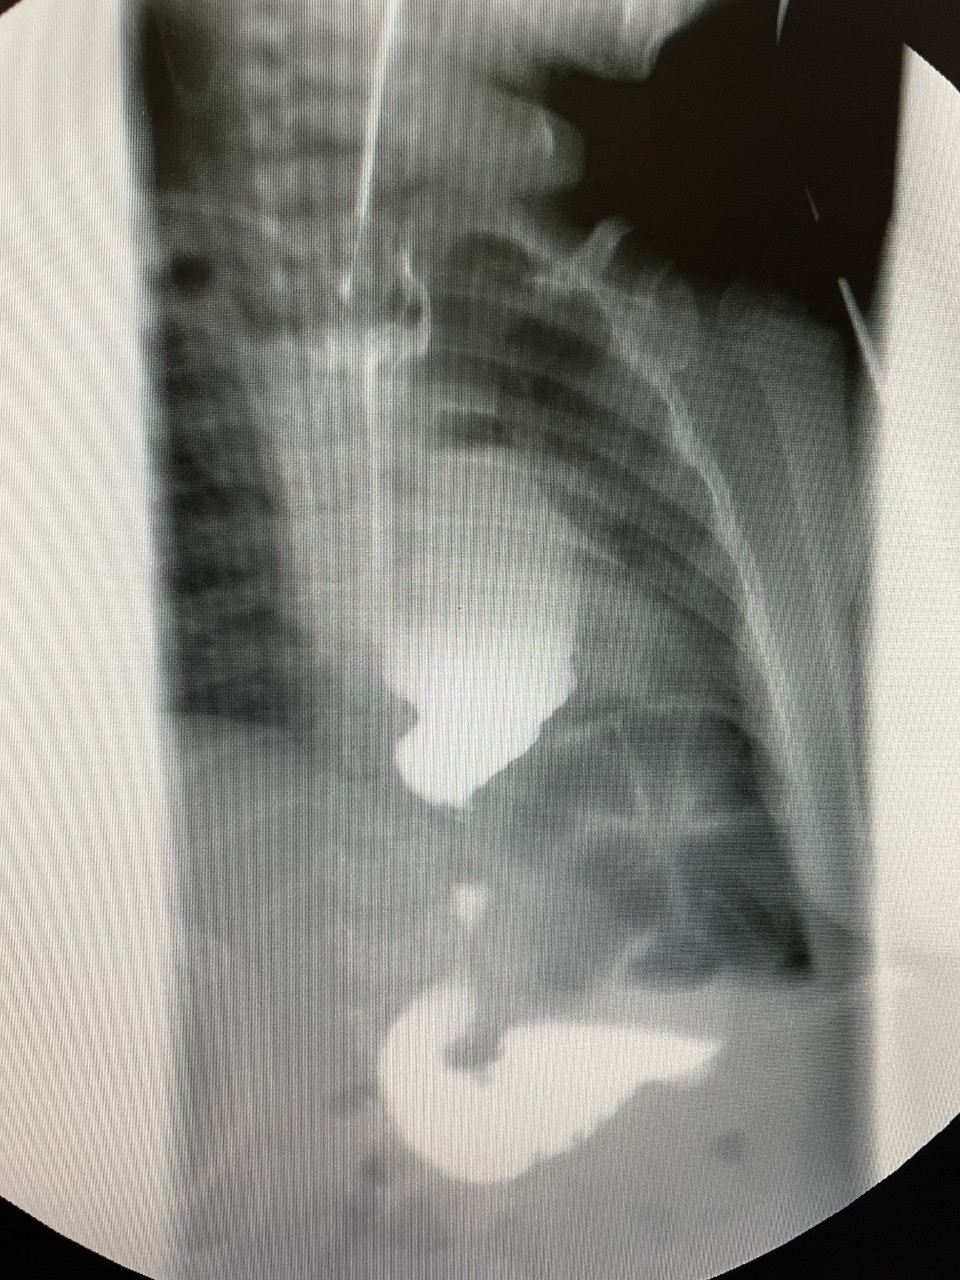

Lent.az-ın məlumatına görə, qida borusunun fistulsuz atreziyası (qida borusunun böyük qisminin anadangəlmə olmaması) ilə doğulmuş uşağa yenidoğulan dövrdə uşaq cərrahı Gündüz Ağayev tərəfindən Ezafaqo və Qastrostomiya əməliyyatı icra olunub.

1 il müddətində mədəyə qoyulmuş rezin boru ilə qidalanan uşaq 1 yaşında növbəti cərrahi əməliyyat üçün "Leyla Medical Center"ə gətirilib və xəstəyə yenə Rusiya Federasiyasının tibb elmləri doktoru Gündüz Ağayev tərəfindən, bu qüsur zamanı Azərbaycanda ilk dəfə olaraq qida borusunun əvəzlənməsi əməliyyatı icra edilib. Əməliyyatda mədə arxa divararalığından, ürəyin, aortanın və traxeyanın arxasından boyuna çıxarılaraq, qida borusunun ucu ilə birləşdirilib.